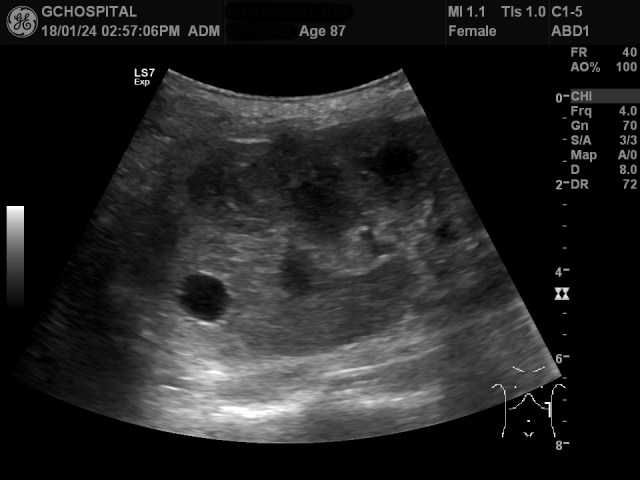

이 환자는 넘어져서 좌측 늑골골절이 의심되어 초음파하신 87세 여자분으로, 늑골골절의 발견을 위해 초음파를 의뢰해서 시행했던 사례입니다. 늑골골절은 발견할 수 없었지만, 여전히 통증을 느끼고 있었기에 옆구리부위의 장기들에 손상이나 이상여부를 확인하기 위해 좌측신장을 보았습니다.

좌측 신장은 흉곽 안에 들어가 있어서 쉽게 확인이 되지 않은 상태였으며, 숨을 최대한 들이마신 상태에서도 흉곽 바깥쪽으로 다 나오지 않았습니다. 좌측신장의 가운데 부위가 검게 잘 보이지 않고 있는 이유는 늑골에 의해 발생한 음영에 의한 것입니다.

호홉을 조절해가면서 늑골에 의해 발생하는 음영을 피해 좌측신장을 확인하면서 몇 개의 작은 단순낭종을 발견했고, 위 영상은 그 중 윗부분에 존재했던 직경 8미리 정도의 낭종을 표시한 것입니다.

이러한 작은 단순낭종이 아래쪽에도 더 있을까 확인해보려 했지만, 좌측 신장이 흉곽 안에 들어있고, 환자분이 고령에 굉장히 깡마른 상태여서 시야가 잘 확보되지 않았습니다. 위 영상에서도 앞서와 비슷한 1센티미터 이하의 단순낭종이 신장 피막 바깥쪽으로 튀어나온 것이 보이지만, 이 외에도 좀 애매하게 안보이는 낭종들이 보여서 선형탐촉자를 갈비뼈 사이로 위치해서 더 확인해봤습니다.